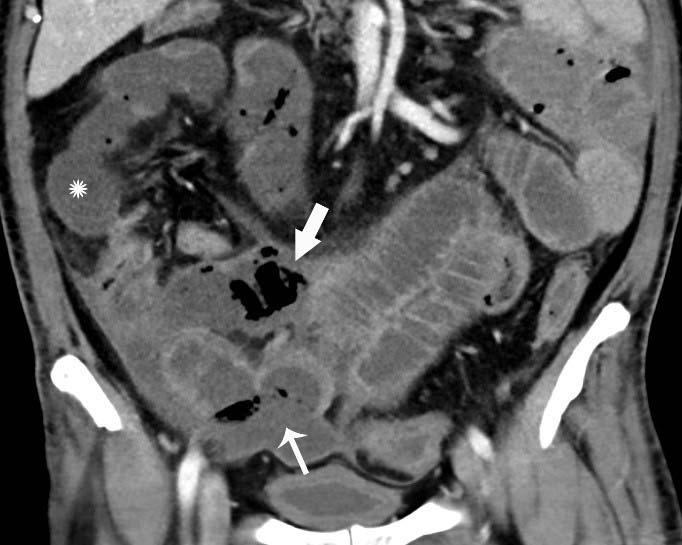

Records showed that 17% of patients had cross-sectional abdominal imaging, including 44 ultrasounds, 42 CT scans, and 1 MRI. Bowel abnormalities were seen on 31% of CT scans (3.2% of all patients) and were more frequent in intensive care unit (ICU) patients than other inpatients. Bowel findings included thickening and findings of ischemia such as pneumatosis (gas in the bowel wall) and portal venous gas. Surgical correlation in four patients revealed unusual yellow discoloration of bowel in three of the patients, and bowel infarction (dead bowel) in two patients.

In two patients who had bowel resection, pathology demonstrated ischemia with patchy necrosis (injury due to reduced arterial flow with patchy areas of cell death). Both had fibrin thrombi (blood clots) in submucosal arterioles (small arteries in the bowel wall), suggesting bowel ischemia in these patients might be caused by these small blood clots. Lung base findings led to a diagnosis of COVID-19 in one patient who presented with abdominal symptoms only. Of right upper quadrant ultrasounds, 87% were performed for liver laboratory findings, and 54% demonstrated a dilated sludge-filled gallbladder suggestive of cholestasis, or a decrease in bile flow.

"Some findings were typical of bowel ischemia, or dying bowel, and in those who had surgery we saw small vessel clots beside areas of dead bowel," Dr. Bhayana said. "Patients in the ICU can have bowel ischemia for other reasons, but we know COVID-19 can lead to clotting and small vessel injury, so bowel might also be affected by this."